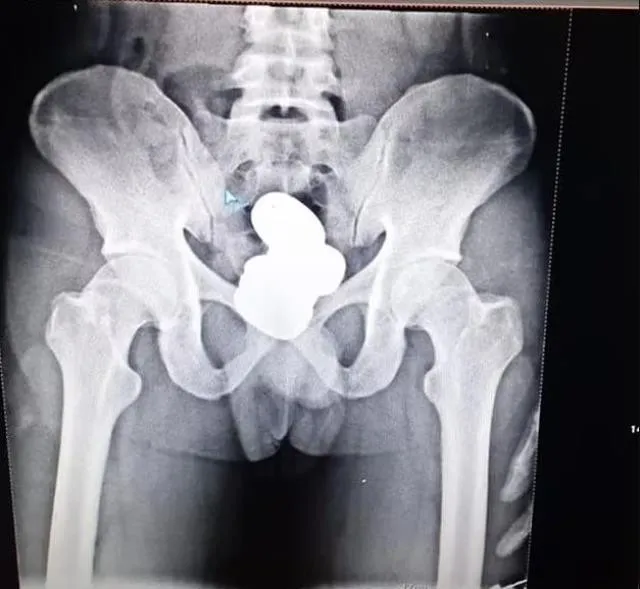

Güvenlik güçleri tarafından gözaltına alınan Mohammad Sharif isimli şahsın makatında dört kapsül haline getirilmiş 850 gram ağırlığında toz altın bulundu.